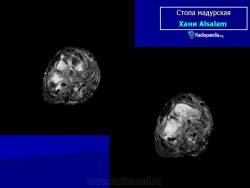

Заболевание прогрессирует как очаговые тканевые образования с формированием опухоли, участков нагноения и рубцов. Иногда формируется множество свищевых ходов, из которых выделяется гной с зернами. Инфекция никогда не распространяется гематогенно, однако может происходить распространение по лимфатическим путям - к региональным лимфатическим узлам и с последующим нагноением. Такие случаи требуют повторных хирургических вмешательств. Вовлеченные ткани могут также вторично загрязняться бактериями. Распространенность поражения мягких тканей лучше всего определять на магнитно-резонансной томографии (МРТ).

Рентгенологическую картину мадурской стопы мы считаем на основании изучения собственных 8 наблюдений и литературных данных чрезвычайно характерной, ничего общего не имеющей с картиной поражения стопы при всех других нозологических формах, в том числе и при актиномикозе. Один лишь взгляд на рентгенограмму достаточен, чтобы поставить диагноз заболевания, разумеется, при условии знакомства с этой болезнью (рис. 258). Эта картина слагается из наличия округлых кистовидных деструктивных очагов, более или менее густо пронизывающих как трубчатые, так и короткие кости стопы, как компактную, так и губчатую костную ткань. Остаются нормальными только фаланги и обычно дистальные концы плюсневых костей, если и не всех. Кости изъедены изнутри и снаружи, крайне истончены, суставные поверхности разъединены, между ними развиваются широкие диастазы. При всем этом глубоком разрушении скелета стопы ее костные элементы удивительным образом все же в основном сохраняют нормальные взаимоотношения, т. е. вся стопа как анатомо-функциональное целое не терпит никакого ущерба. Остеосклероз или периостальные реакции здесь бывают редко, если только нет осложнения остеомиелитом, а последний как раз никем достоверно при мицетоме стопы и не доказан. Об остеопорозе или атрофии костей, равно как об изменениях невротрофического характера в обычном смысле этих понятий, сказать что-нибудь определенное нет возможности, настолько глубоки изменения, которые претерпевает структура скелета стопы из-за основных деструктивных явлений.

Мицетома

Мицетома

Рисунок 21.21

Случаи и цифры